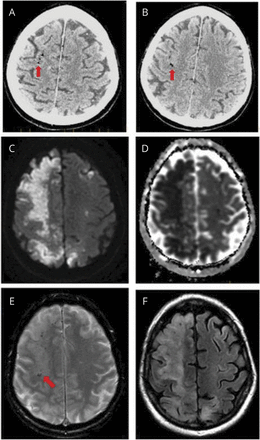

最后病理结果显示积极的b细胞淋巴瘤。神经病学治疗开始之前,咨询了急性post-tussive晕厥其次是左首页胳膊和腿的弱点与NIH卒中量表(署)2分。心电图和血压,手指贴,都是正常的。急性梗塞被怀疑,因为病人是现成抗凝最近的位置。CT头没有任何缺血。CT扫描后不久,病人开发正确的目光随着全球失语症和左半身麻痹导致署16。CT血管造影术(图)没有任何动脉异常;然而,许多分散,1毫米,hypodense焦点被认为正确的大脑中动脉的领土,假定代表空气栓子。核磁共振成像(图)证实了一个巨大的右侧急性梗塞无出血性转换。经胸廓的超声心动图显示正常射血分数没有右至左分流的证据。脑电图显示中度脑病没有癫痫样的变化。

(A, B)初始干头部CT显示空气栓子(红色箭头)。(C, D) MRI大脑,没有对比。扩散和表观扩散系数表明限制显示梗塞组织在右大脑中动脉(MCA)以及一些小左额叶和后壁梗塞。梯度回波序列回忆(E)演示了microhypointensities沿着正确的MCA领土(红色箭头),可能证明空气栓子CT上看到。Fluid-attenuated反转恢复(F)展示了细胞毒性水肿。

最初的头部CT和造影CT扫描均显示线性分散hypodensities沿颈内动脉arterywatershed分布主要集中在右半球。这些病变的密度与空气或脂肪是相一致的。知道病人没有任何外伤或骨折,脂肪栓子是不可能的。由于恶性肿瘤,我们认为嫁妆综合症的可能性,但相信这是不可能的,因为往往出现粘液性肿瘤与淋巴瘤类型。9成像的hypodensities并不符合纤维蛋白或富含血小板凝块,所产生的嫁妆和其他hypercoagulable综合症。脑部MRI表现出大的右半脑急性梗死以及小左半球梗死灶。梯度回波序列表明线性hypointensities与空气栓子的CT扫描,在先前的研究中。10此外,在我们的病人,可见T1 postcontrast焦旋转的(leptomeningeal)增强。这可能是由于对比泄漏进入脑脊液从损坏的船只。皮层的参与以及周围的皮质下区域出现在T1, T2,和fluid-attenuated反转恢复序列,进一步支持动脉梗塞的病因。相反,如果静脉病因,我们怀疑受灾地区将是肤浅的和皮质与一个完全不同的模式。